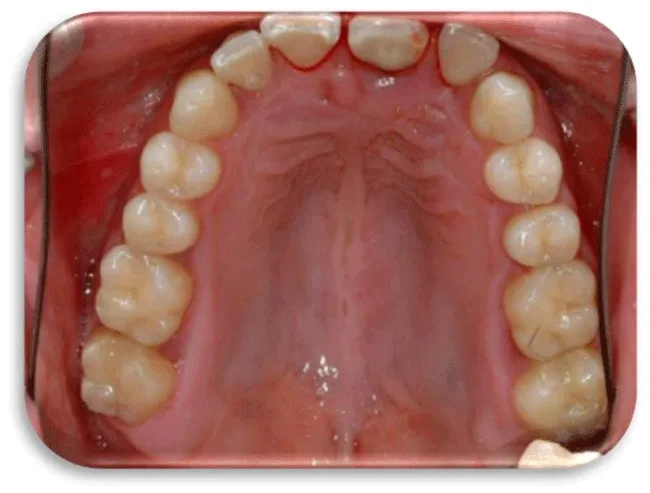

Two dental titanium implants were placed in a 37 years old, male patient. These two dental titanium implants were placed one year ago and their position is 36, they compensate the lower left first molar. The patient come to dental office on control because he felt pain in the area of dental implants. The pain, except during mastication, was also manifested during the brushing of the teeth, and was accompanied by bleeding from the gums. Gingiva was hyperemic and oedematous (Figure 36), and X-ray control images were also made, which can be seen below (Figure 37-40). During the process of probing, the dental probe drowned in bone pocket around the dental implants at a depth of 10 mm.